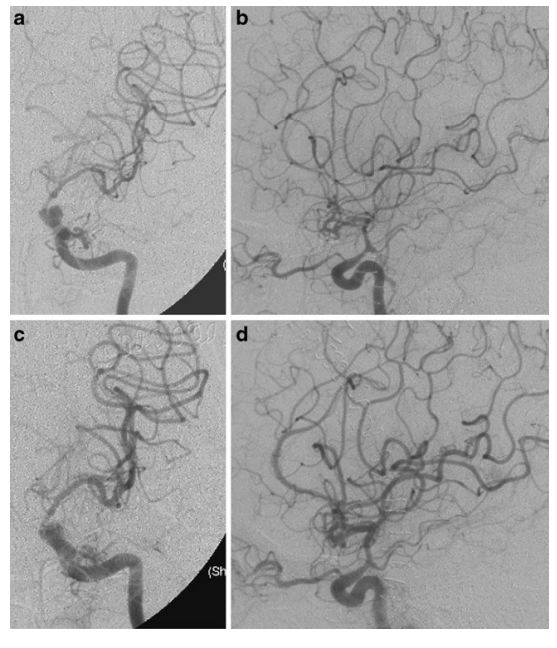

Figure 1. Angiograms from Patient 12.A 42-year-old woman developed gradual onset of aphasia and right-sided weakness (hemiparesis) on day 8 following surgical clipping of an anterior communicating artery aneurysm. Angiograms showed severe vasospasm in the left internal carotid artery (ICA), anterior cerebral artery (ACA), and middle cerebral artery (MCA). Her symptoms improved immediately after receiving intra-arterial colforsin daropate hydrochloride (IAC treatment).a–b: Left carotid angiograms on day 8 showing severe vasospasm in the ICA, ACA, and MCA.c–d: Angiograms after IAC treatment showing significant vessel dilation in both proximal and distal segments.